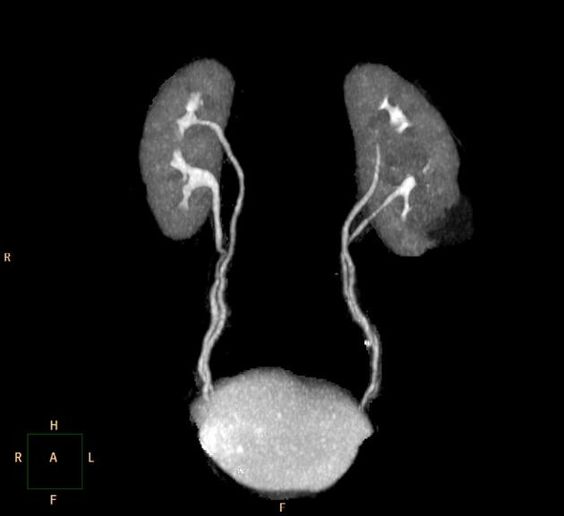

Что показывает МРТ мочеточников

В первую очередь необходимо отметить, что магнитно-резонансная томография мочеточников выполняется в комплексном обследовании почек и мочевыводящих путей, как самостоятельный метод диагностирования невозможен.

При помощи магнитно-резонансной томографии удается оценить состояние органов и выявить имеющиеся патологии:

- оценить топографическое положение и выявить аномалии развития данного органа;

- оценка кровоснажения мочеточников;

- выявить патологические очаги и имеющиеся зоны поражения в мочеточниках;

- определить наличие новообразований, его размеры;

- оценить функциональность данного органа.